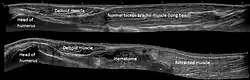

Panoramic ultrasonography of a proximal biceps tendon rupture. Top image shows the contralateral normal side, and lower image shows a retracted muscle, with a hematoma filling out the proximal space.

Panoramic ultrasonography is the digital stitching of multiple ultrasound images into a broader one.[101] It can display an entire abnormality and show its relationship to nearby structures on a single image.[101]